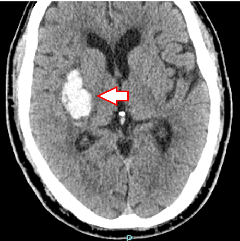

脳内出血

高血圧が原因となり、もろくなった脳内の小血管に動脈瘤が破れて脳内に出血します。出血の部位やサイズによって、開頭血腫除去術・定位血腫吸引術や脳室ドレナージ術などが行われます。

(下図1)右被殻出血で突然の左半身のまひが起こった症例です。

(下図2)脳皮質下での出血が脳室まで広がった脳室穿破の症例です。

右被殻出血

脳皮質下出血